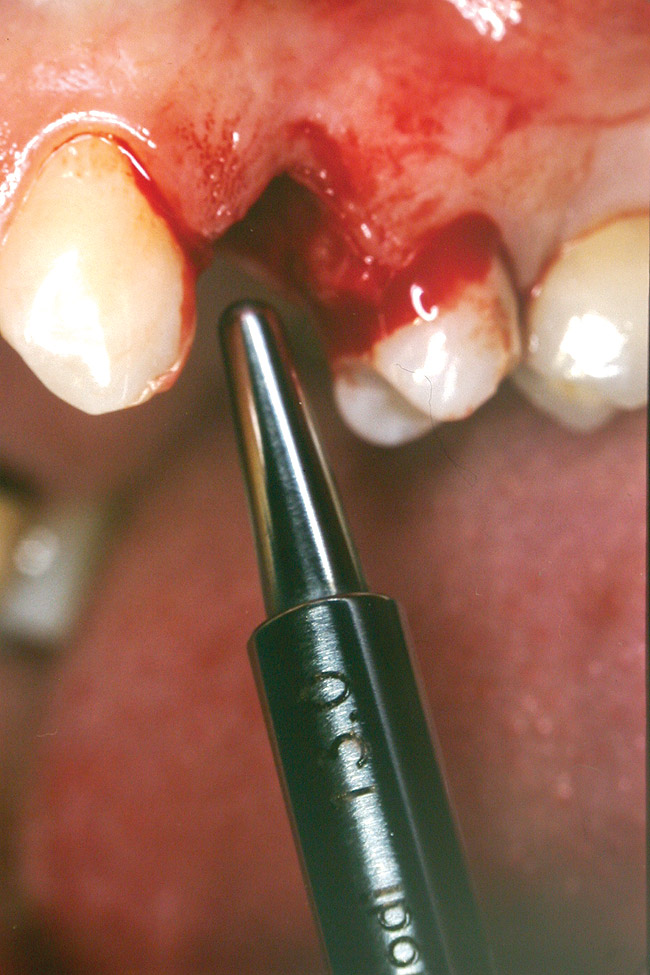

Case 3

A 53-year-old female was referred for evaluation of a fracture of tooth No. 24. The tooth had been treated endodontically 5 years prior. The radiograph revealed a complete fracture of the tooth involving the crown (Figure 12). Tooth extraction and immediate placement of a an implant that was 10 mm in length and 3.75 in diameter was planned.

At the time of surgery, the tooth was extracted without harvesting any mucosal flap because the implant site was prepared by means of a pilot drill bur (Figure 13) and alternating osteotomes (Figure 14A and Figure 14B). The implant was positioned and showed primary stability. The implant was loaded 2 days after surgery. Then, splinted PFM crowns supported by custom gold abutments were delivered. At 6 months posttreatment, the radiograph revealed no bone resorption and the clinical result was optimal (Figure 15A and Figure 15B).

Figure 13  The drill bur was used to start the implant site preparation.

Figure 13